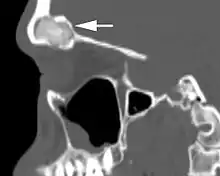

When performing imaging studies, bone windows in computed tomography studies are the best. The lesion is usually identified as a well demarcated, expansile mass with an ossified rim at the periphery. Calcifications are noted throughout. MRI shows a variable finding depending on T1 or T2 weighted images, dependent on the amount of bone to fibrous connective tissue ratio.[2]